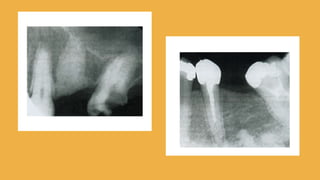

R a d i o l o g í a

Puede identifcar uno de varios patrones,

a veces la anormalidad es

uniformemente opaca; también puede

ser una transparencia periférica con

centro opaco; otras la perifería es opaca

con centro transparente, o bien, puede

estar compuesta de masa opacas

confluyentes o lobuladas.